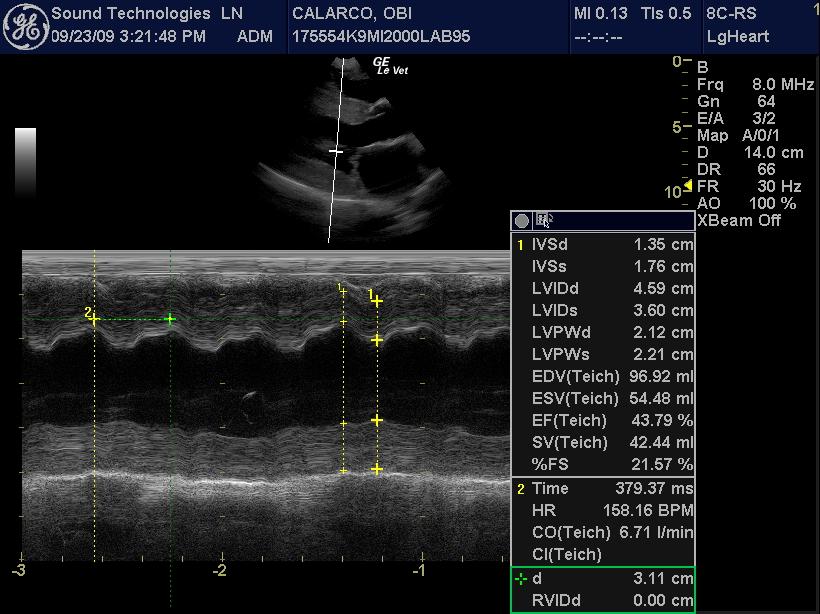

An 11-year-old MN Labrador retriever was prestented for excercise intolerance, lethargy, depression, vomiting and diarrhea. The physical exam was unremarkable other than a grade 2 left sided heart mumur at the heart base and irregular heart beat with pulse deficits. CBC, CHEM, UA, and acth stim were all normal.